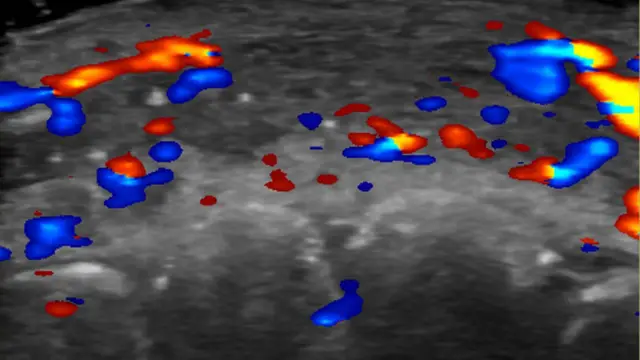

Pesquisadores usaram um ultrassom para estudar 100 casos de preenchimento que deram errado.

Clínicas estão sendo aconselhadas a fazer uma ultrassonografia antes de iniciar o procedimento no rosto, para evitar dandos a artérias próximas.

Em quase metade dos casos avaliados, ultrassonografias mostraram ausência de fluxo sanguíneo em vasos pequenos que conectam artérias superficiais àquelas mais profundas do rosto.

E em um terço dos pacientes, fluxo sanguíneo estava ausente nos principais vasos sanguíneos.

Para evitar complicações, ela aconselha que as clínicas realizem ultrassonografias para planejar onde o produto vai ser injetado.

Se complicações aparecerem, a ultrassonografia pode guiar o tratamento.

“Se os preenchimentos não forem guiados por ultrassonografias, o tratamento é feito apenas com base nos sinais clínicos e o produto é injetado às cegas”, afirma Sigrist.

“Mas se nós temos o ultrassom, podemos tratar o local exato onde as obstruções ocorrem.”

Assim, em vez de inundar a área com um medicamento chamado hialuronidase para dissolver o preenchimento, os médicos podem realizar injeções guiadas que utilizam menos hialuronidase e proporcionam melhores resultados de tratamento, afirma.